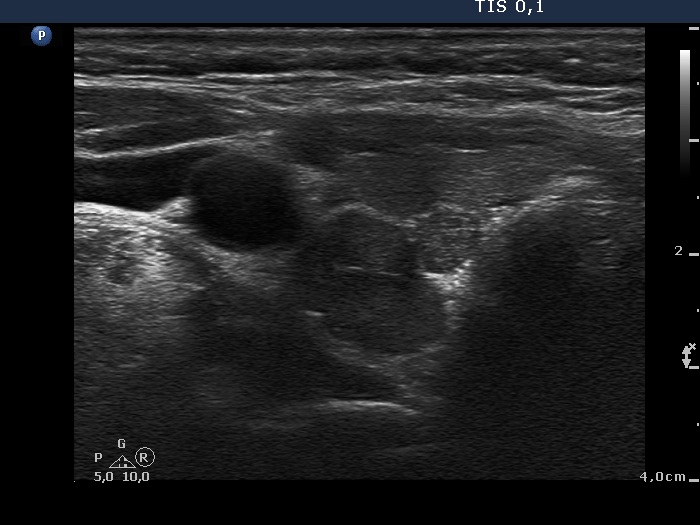

Ultrasonography. The thyroid was minimally-moderately hypoechogenic. There was a hyperechogenic nodule in the central part of the right lobe while several small insignificant lesions in the left thyroid. There was a hypoechogenic mass in the border of the middle-lower part of the right lobe dorsolateral. The lesion presented no vascularity.

Wash-out results of the hypoechogenic lesion: thyroglobulin 154 pg/L, parathormone 390.5 pg/mL.

Scintigraphy disclosed parathyroid lesion corresponding to the mass in the lower-dorsal part of the thyroid.